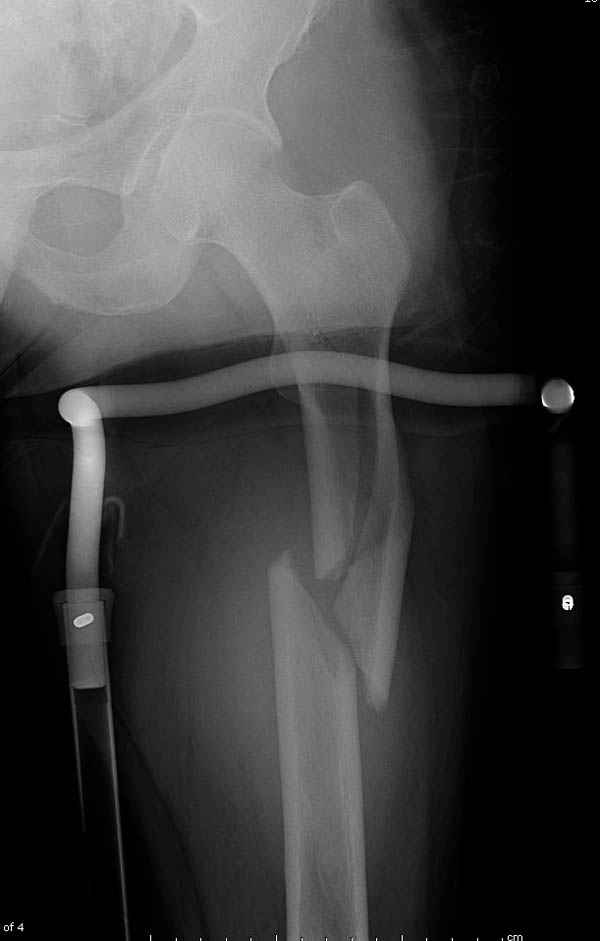

Учитывая, что случай ургентный, больной поступил вечером, не стали делать вытяжение и срочно провели операцию по фиксации перелома бедра антеградным штифтом Versa Nail от DePuy.

Для профилактики дальнейшего раскола в шейке предварительно во время проксимального рассверливания спереди и сзади провели временные спицы, которые в дальнейшем были заменены на шурупы (miss nail method)

Обычная спасательная фасциотомия для обычного больного в этом случае было бы приговором, поэтому несмотря на высокие цифры компартментального мониторинга больного оставили под наблюдением с обкладкой конечности льдом.

Кровотечение удалось контролировать, и больной через пару дней выписан на амбулаторное лечение.